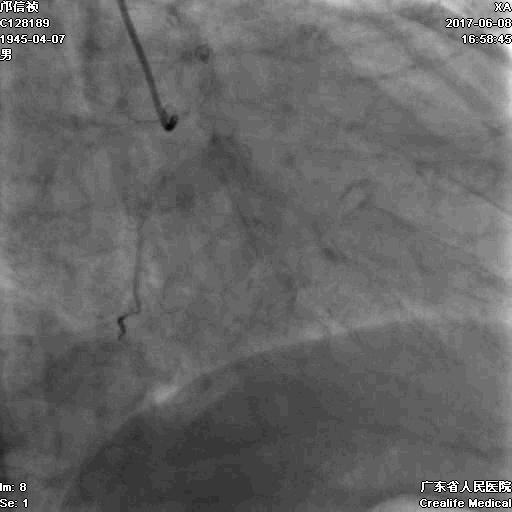

RRA:6F AL0.75 GC –RCA;

RFA:7F XB 3.5 GC—LCA 150cmcorsair

正向130cmFinecross微导管支持下尝试送PILOT150、Gaia 2导丝无法通过RCA闭塞段

SION导丝通过侧枝

逆向导丝:更换Gaia2

正向导丝:Gaia2,PILT150

正向导丝knuckle

2.5*15mm球囊扩张,逆向导丝尝试,但未能进入正向GC